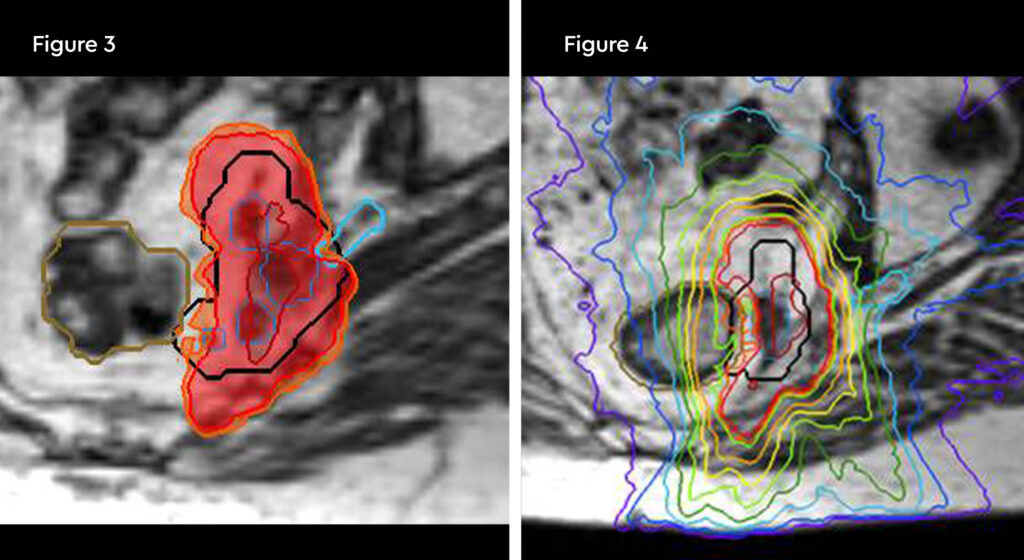

Fig 1 and 2: Planning. 100% isodose in red shaping off sacral nerve root, and orange contour is the rectum remaining tolerance dose of 28.8 Gy. Down to the 50% isodose in green

Fig 3 and 4: Fraction 1. Change in rectum position and 120% hotspot over the gross tumour volumes (GTVs)

Fig 5: Fraction 3. Hot spot 120% directly in gross tumour volume (GTV)

Fig 6 and 7: Fraction 5. Nerve inside the planning target volume (PTV) being spared the 100% isodose